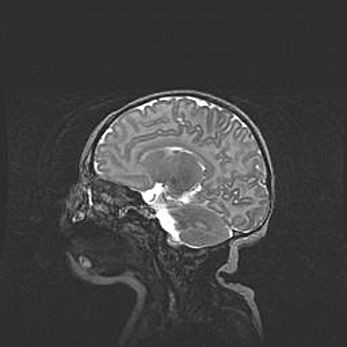

Неполная лизэнцефалия (пахигирия). Открытая гидроцефалия.

Возраст: 17 дней

Вес: 3110 г

Пол: мужской

Окружность головы: 33,5 см

Срок гестации: 35-36 недель

Лизэнцефалия—недоразвитие корковой пластинки и мозговых извилин в результате нарушения миграции нейронов коры. Поверхность мозговых полушарий гладкая. Микроскопически выявляется отсутствие нормальных слоев коры и скопление групп нейронов в подкорковом белом веществе.

Пахигирия—уменьшение числа вторичных извилин. В пораженном полушарии нервные клетки образуют толстый недифференцированный слой с неправильно расположенными нервными волокнами и группами гетеротопных клеток. Нервные клетки незрелые. Белое вещество истончено. При этом нередко аномально развит корково-спинномозговой путь.